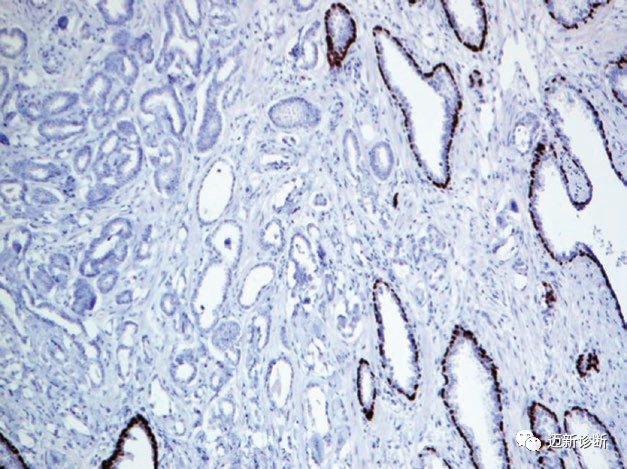

图片

图1. 基底细胞癌,EP-CAM强阳性表达。

图2. 前列腺组织免疫组化p63,正常腺体周围有阳性着色,而肿瘤性腺体周围为阴性。